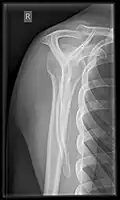

X-ray

Projectional radiography views of the shoulder include:

- AP-projection 40° posterior oblique after Grashey

The body has to be rotated about 30 to 45 degrees towards the shoulder to be imaged, and the standing or sitting patient lets the arm hang. This method reveals the joint gap and the vertical alignment towards the socket.[26]

- Transaxillary projection

The arm should be abducted 80 to 100 degrees. This method reveals:[26]

- The horizontal alignment of the humerus head in respect to the socket and the lateral clavicle in respect to the acromion

- Lesions of the anterior and posterior socket border, or of the tuberculum minus

- The eventual non-closure of the acromial apophysis

- The coraco-humeral interval

- Y-projection

The lateral contour of the shoulder should be positioned in front of the film in a way that the longitudinal axis of the scapula continues parallel to the path of the rays. This method reveals:[26]

- The horizontal centralization of the humerus head and socket

- The osseous margins of the coraco-acromial arch and hence the supraspinatus outlet canal

- The shape of the acromion

This projection has a low tolerance for errors and, accordingly, needs proper execution.[26] The Y-projection can be traced back to Wijnblath’s 1933 published cavitas-en-face projection.[27]

-

CR. shoulay film. -

Transaxillary conventional radiography -

Y-projection conventional radiography